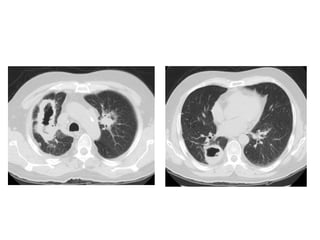

c) Cryptogenic Organizing Pneumonia (COP) : Ground-

glass (peribronchial, peripheral not subpleural) &

Consolidation

-The lung abnormalities show a characteristic peripheral or

peribronchial distribution, and the lower lung lobes are

more frequently involved

-In some cases, the outermost subpleural area is spared

-Typically, the appearance of the lung opacities varies from

ground glass to consolidation; in the latter, air

bronchograms and mild cylindrical bronchial dilatation

are a common finding